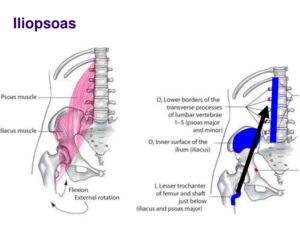

- Mostra organi interni come il fegato, la milza, i reni e lo stomaco.

- Evidenzia la colonna vertebrale (vertebre lombari da L1 a L5) e i muscoli associati come lo psoas.

- Include riferimenti a strutture vascolari come l’aorta e strutture ossee come l’acetabolo.

- Presenta etichette per vari organi pelvici e muscoli, inclusi la vescica e il prostata.

Manca solo l’evidenza dei vasi arterio-venosi e delle innervazioni. Maderu